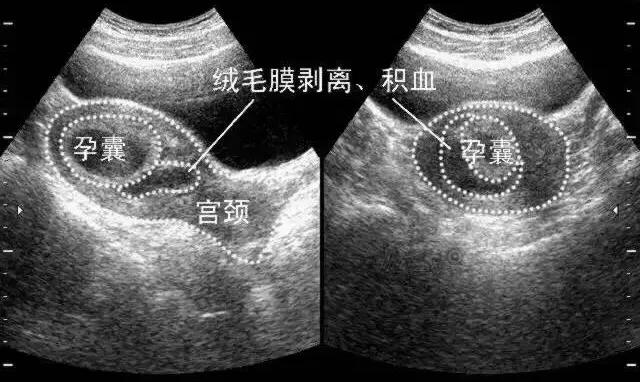

先兆流产:在妊娠前半段,当阴道出血或有血样分泌物,是临床推断为先兆流产。通常是先流血数小时,或数天后出现腹部痉挛性疼痛,早孕期间四五个孕妇中就会有一个出现阴道点状出血。这些孕妇中大概有一半会流产。未流产的妇女面临着不良的分娩结局,如不足月分娩,低体重儿,围生期死亡。对于伴有阴道流血的妇女鉴别诊断包括生理流血,宫颈损伤,宫颈息肉,宫颈癌。这些原因造成的流血通常不会伴随下腹痛和持续的背痛。很重要的一点,是应该考虑异位妊娠。